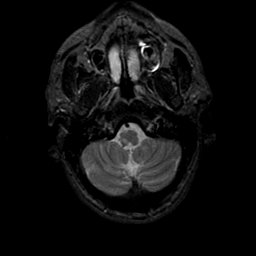

MR Study #21, November 3, 1991 -- Slice #6